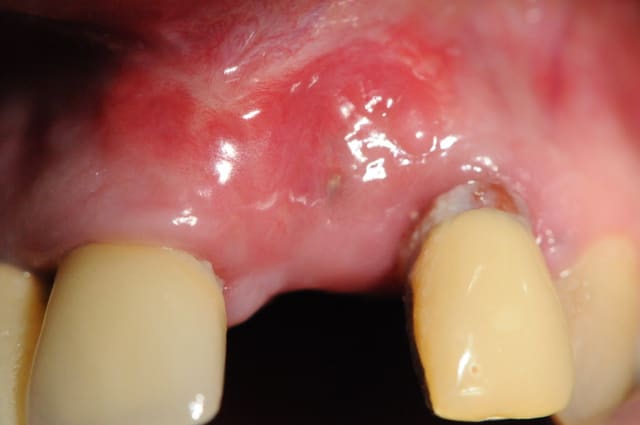

Voila un exemple de conjonctif pédiculé palatin.

Les gros avantages par rapport à ta technique sinclair sont :

1- mobilisation d'un plus gros volume de tissus pour gonfler en vestibulaire.

2- cicatrisation de première intention au niveau du palais puisque l'ensemble du site prélevé est couvert par ta fenêtre d'accès

3- peu de suite post opératoire.